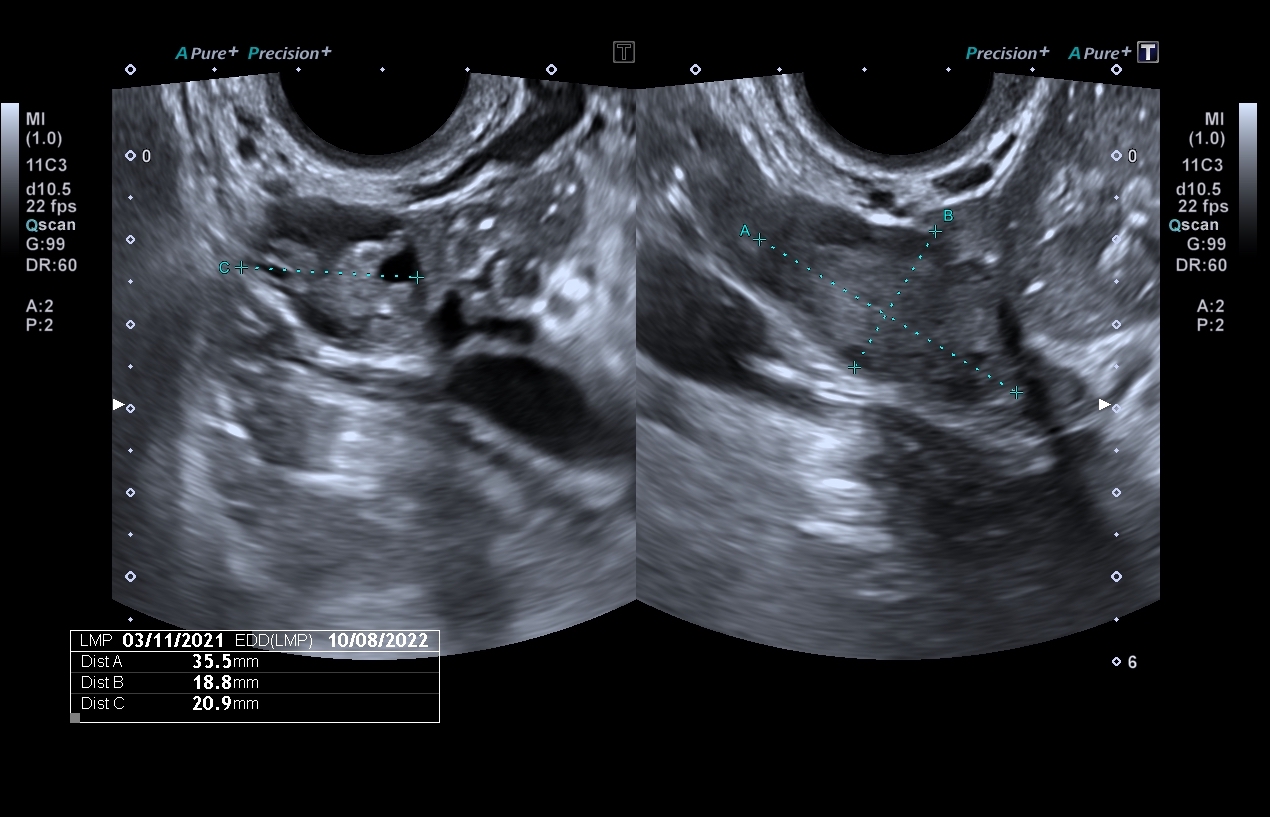

Se presenta a la consulta una paciente que refiere una amenorrea de 7 semanas. No presenta antecedentes de relevancia. En el examen ultrasonográfico se visualizan las siguientes imágenes (figs. ) ¿Cuál es su presunción diagnóstica? a) Las imágenes corresponden a la fase progestacional del ciclo menstrual normal, ya que el endometrio se encuentra engrosado y se visualiza el cuerpo lúteo en uno de los ovarios. b) Las imágenes son compatibles con el diagnóstico de un embarazo ectópico. c) Las imágenes son signos de alarma de muerte embrionaria precoz por lo que se solicita repetir el estudio en 7 a 10 días.

Los hallazgos anexiales son tal vez los más representativos para el diagnóstico del EE. Se debe destacar que el 95% de los EE son tubarios y que las trompas de Falopio no se visualizan en condiciones normales. En el 70-80% de los EE se puede observar un cuerpo lúteo ipsilateral a la trompa afectada. El diagnóstico de EE queda establecido si se observa un saco gestacional con un saco vitelino y/o un polo embrionario con o sin actividad cardíaca. Esta situación solo se observa en el 10-25% de los casos. En cambio, se define como probable EE la presencia del signo de la gota o el signo del bagel. El signo de la gota o blob sign se refiere a la presencia de una masa heterogénea que corresponde al trofoblasto y coágulos, adyacente al ovario y con movilidad independiente. El signo del bagle hace referencia a un anillo hiperecogénico con un centro anecoico o hipoecoico. Este último hallazgo posee una sensibilidad del 89-100% y una especificidad del 92-99% para el diagnóstico de EE. Como hallazgos peritoneales se puede observar la presencia de líquido hemorrágico con un patrón de vidrio esmerilado en el fondo de saco de Douglas o a nivel del espacio de Morrison.

En relación al caso presentado en el número anterior, la respuesta correcta es la b: imágenes compatibles con un embarazo ectópico. A las 7 semanas de amenorrea se debe observar un saco gestacional con un embrión intrauterino. A nivel de los anexos se puede visualizar un cuerpo lúteo pero ante la falta de la imagen uterina, se deben estudiar con mucha cautela los anexos por la posibilidad de tratarse de un EE. En este contexto, es fundamental una correcta anamnesis, el examen físico y la determinación seriada de la subunidad beta de la hormona gonadotrofina coriónica.